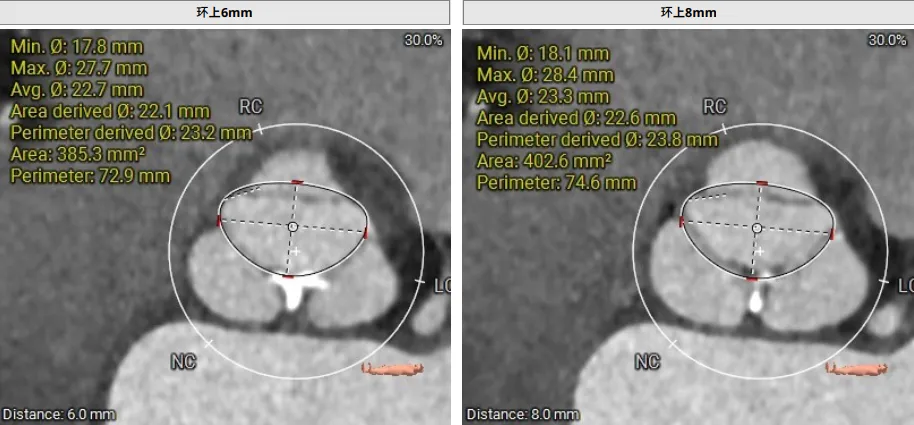

患者为主动脉 Type I 型二叶瓣,左无瓣叶交界处钙化融合,瓣叶稍增厚;存在三个瓣窦,分布较均匀;主动脉瓣环周长折算直径27.0mm;双侧冠脉开口高度可LCA:12.9mm;RCA:15.1mm;双侧冠脉开口高度可,右侧冠脉开口处扩张,双侧冠脉点状钙化;最佳投射角度:右窦中心位:CRA:1°/RAO:2°(其他参考角度如下图);左室主动脉夹角为159°; 模拟切口位置:第6-7肋间;模拟输送器角度为149°。